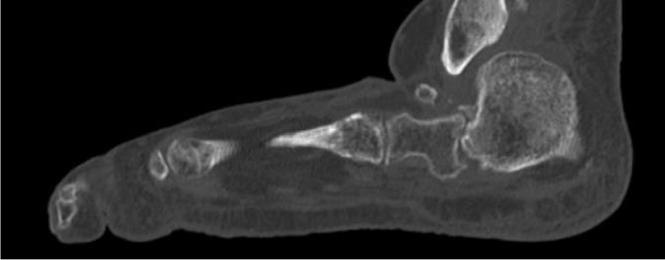

4fordatacollectiontools.)Thrombotic eventswerecollectedduringindexhospitalizationandat30 and90daysafterdischarge.Wedefinedthromboticeventsas deepveinthrombosis(DVT),pulmonaryembolism(PE), ischemicstroke,myocardialinfarction,orotherarterialor venousthromboembolicevents.Doortoneedletimewas definedastimefromhospitalpresentationtoreceiptof reversalagent.OnsettoCTtimewascalculatedusingthe differencebetweeninitialCTandtimeofbleedingonset, wheretheybothexisted;onsettoCTtimefortheremainder ofcaseswasdeterminedbycombiningcategoricalonsetto presentationtime(<6,6–12,12–24,24–48,and >48hours),

usingthemediantimeforeachcategory,withdoortoCT time.Wedefinedallstudydataandvariablespriorto initiatingthestudyandtrainedourdataabstractorsusinga libraryofdefinitions(see Supplement1).Weperiodically monitoreddatacollectionandprovidedfeedbacktothedata abstractorsduringandafterdatacollectionandentry regardingmissing,conflicting,orobviouslyerroneousdata. Thenumberofdataabstractorsateachinstitutionvaried from1–3.Thedataabstracterswerenotblindedtotherapy.

Outcomes

Wedevelopedallstudyoutcomesapriori.Theprimary outcomeswerepresenceofestimatedtimesfromlastdoseof FXa-Iandtimefrombleedingonsettoadministrationof 4F-PCCorandexanetalfa.Secondaryoutcomeswere hemostaticefficacyasdefinedbytheANEXXA-4criteria,23 survivaltohospitaldischarge,thromboticeventsduringthe indexhospitalizationandat30and90days,andrebleeding eventssuchasICH,rectalbleeding,melena,orhematemesis.

DataAnalysis

Weuseddescriptivestatisticstosummarizethedata. Categoricaldataarepresentedasnumbersorpercentages andcomparedbetweengroupsusingchi-squareorFisher exacttestsasappropriate.Continuousvariablesare presentedwithmeansandstandarddeviationsormedians andinterquartileranges(IQR)basedontheirdistribution andcomparedwith t -testsortheMann-WhitneyUtests,as appropriate.Becausethiswasapilotstudy,noformalsample sizecalculationwasperformed.Wechosetoinclude25 patientsineachofthefourstudysubgroups:ICHtreated withandexanetalfa;ICHtreatedwith4F-PCC;GIBtreated withandexanetalfa,andGIBtreatedwith4F-PCC.An exploratoryPSMmodelwasconstructedtoestimatetheodds ofexcellent/goodhemostaticefficacyinpatientstreatedwith andexanetalfaor4F-PCCadjustingforage,gender, comorbidities,timefromlastdoseofFXa-I,time frombleedonsettotreatment,andindication foranticoagulation.